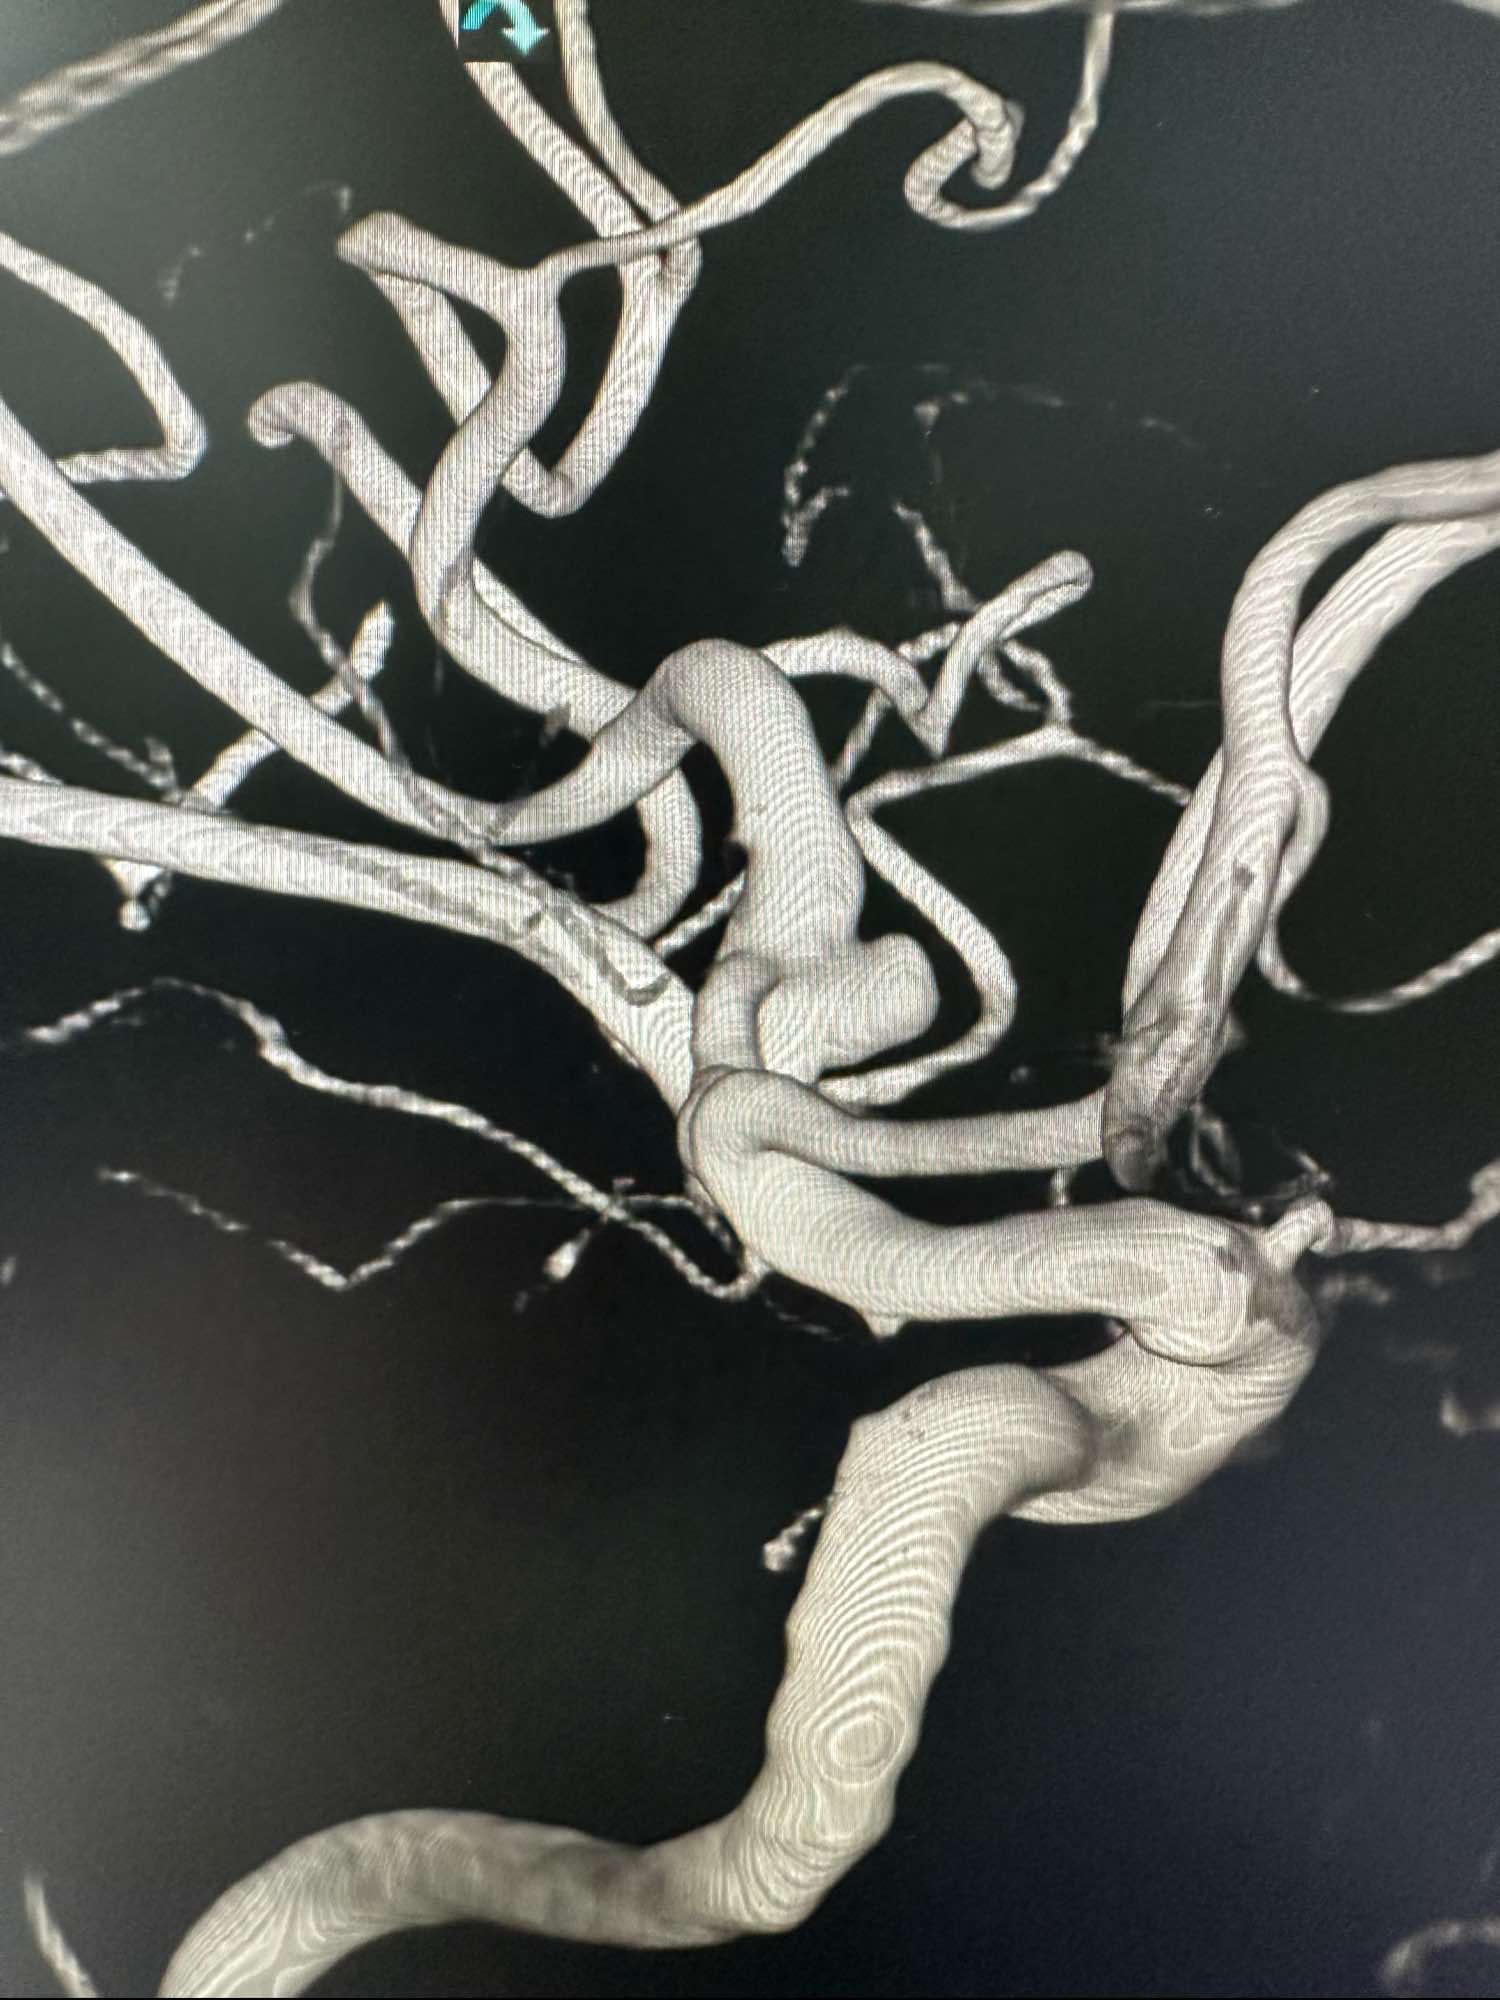

左侧颈内动脉术前3D图像

另外一个角度,动脉瘤大小约3mm左右,宽颈

另外一个角度